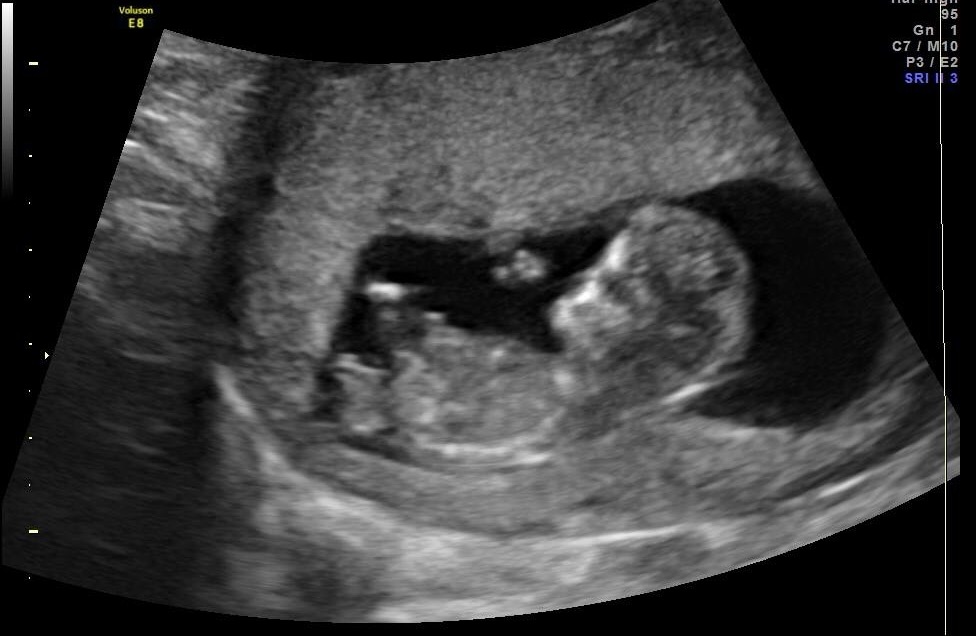

I know it's really too early. But I also know there are great gender guessers out there.

Sonographer examined for an hour in total, and was "leaning" girl.

He confirmed gender in My last pregnancy at 11 weeks 5 days